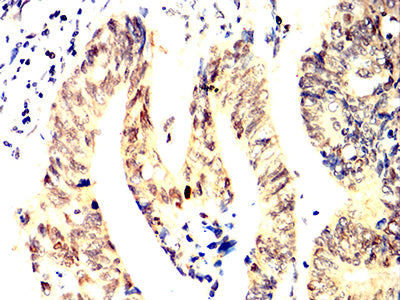

Immunohistochemical analysis of paraffin-embedded human prostate cancer tissues using ACHE mouse mAb with DAB staining.

Immunohistochemical analysis of paraffin-embedded human rectum cancer tissues using ACHE mouse mAb with DAB staining.